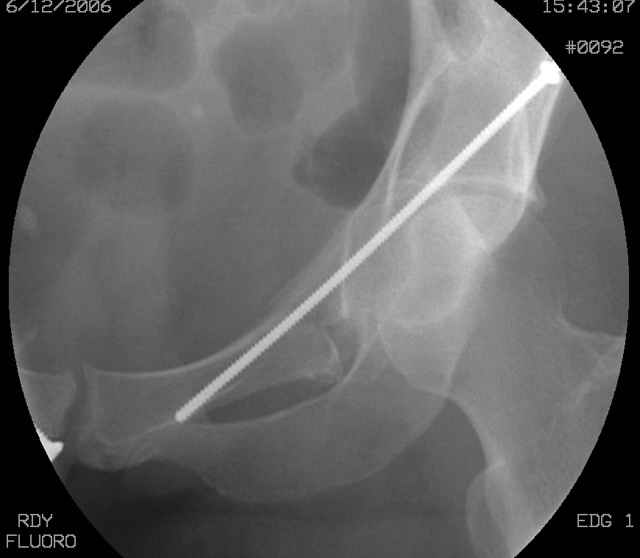

The 2nd example is of a motorcyclist with a transverse fracture-dislocation...he had a closed attempted reduction and placed in traction but the manipulative reduction was not concentric (not unusual for this injury pattern)...so the traction was adjusted to be just enough to disengage the head from the fracture (12#) until he could be cleared for surgery one day after injury...he was treated "urgently" then with a prone KL, clean the fracture, reduce and clamp it, screw it, support with a balanced plate, close, and enjoy...2-3hours, 400cc EBL, blah, blah, blah..

Here's a pic from the foot of the bed and you can see the clamp in the wound and the knee is extended so he must've had a tight rectus. The C-arm is rolled back to an obturator oblique image to reveal the anterior column...we put a slight outlet tilt to combine the images and give a better view of the anterior column...we can see the posterior column limb reduction in the wound, we can palpate the quadrilateral surface limb, and the image demonstrates the anterior column portion...you can adjust the tilt and rotation to image tangentially to the fracture plane if you'd like. We've inserted a 2mm K wire to site the starting point and aim/orientation for the drill and screw

Prone Imaging